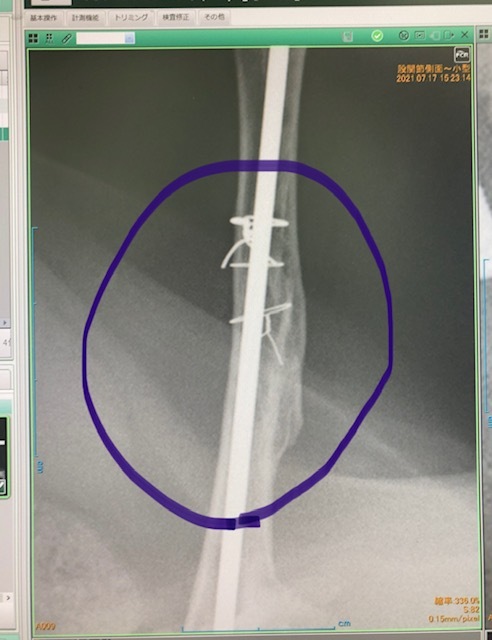

本日、レイちゃんのボルト摘出、避妊手術、血液検査等を行なってきました。先生曰く、問題なく骨が接合しており無事にボルト摘出を行えました。去勢手術も同時に行って頂きました(レイちゃんの負担になるかとも懸念しましたが麻酔が効いている間に一緒に行う事がベストと判断)。血液検査も行い、心配していた猫エイズに関しても陰性でした。2週間後に抜糸のみありますがこれでひとまずは無事に骨折治療を終える事が出来ました。皆様の篤いご支援に支えられた事に対し改めて深い感謝の意を申し上げます。有難うございました。明日以降順次ご支援頂きました皆様へリターン報告に入らせて頂きます。お待たせして申し訳ございませんがどうぞ宜しくお願い致します。

骨盤部分もしっかり接合(左)、左大腿骨も接合(右:太くなってます)していました。